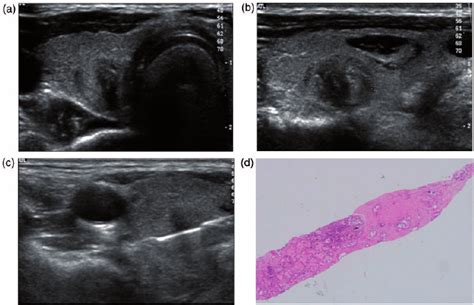

The american thyroid association guidelines taskforce. In some cases, the specimens may be inadequate and the procedure may have to be. The radiologist will insert the needle through the skin under direct imaging guidance, advance it to the site of the thyroid nodule and aspirate samples. The thyroid's job is to make thyroid hormones, which are secreted into the blood and then carried to every tissue in the body. Only a small percentage of thyroid nodules turn out to be cancer. Medicine to numb the area may or may not be used. The needle is placed into the nodule several times and cells are aspirated into a syringe. Only five studies have been published on fna of childhood thyroid nodules. It is important to identify a cancerous nodule as soon as possible, so that you can begin treatment quickly. Explore other smart treatment options, see research evidence, and find out about people's experiences with many popular treatments, including feedback from patients and professionals. Typically, the biopsy is performed under ultrasound guidance to ensure accurate placement of the needle within the thyroid nodule. Representative= includes muscularis mucosae also, fixation on a flat surface=better orientation of the. Why might i need a thyroid fine needle aspiration biopsy?

A fine needle aspiration (fna) biopsy or thyroid biopsy, is usually carried out to determine the nature of the cells in a thyroid nodule. What is a fna biopsy and what is ultrasound is used to guide the biopsy so the doctor can see the needle going into thyroid nodule. The review provides information for indications and contraindications for the procedure. Traditionally, fnab results are divided into four categories: Inadequate or nondiagnostic, benign, indeterminate (otherwise described as suspicious for neoplasm). Some mild pain can be expected after needle. The thyroid's job is to make thyroid hormones, which are secreted into the blood and then carried to every tissue in the body. Management guidelines for patients with thyroid nodules and differentiated thyroid cancer. Medicine to numb the area may or may not be used. Only five studies have been published on fna of childhood thyroid nodules. The american thyroid association guidelines taskforce. Fine needle biopsy of a thyroid nodule fine needle aspiration of the thyroid email this page to a friend share on facebook share on twitter bookmark & share. The definitive diagnosis of a thyroid nodule is made by fine needle aspiration (fna) biopsy.